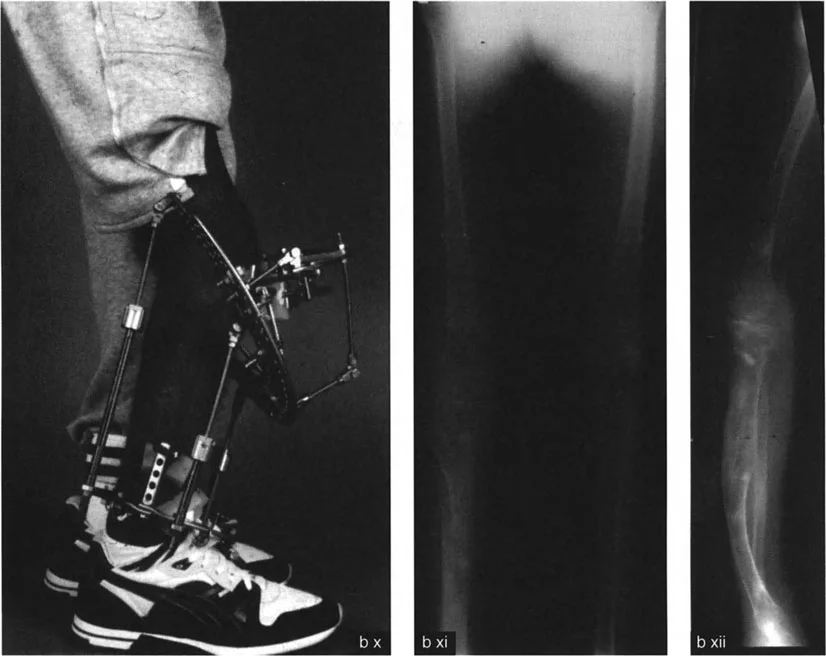

خيارات العلاج المتقدمة لتصحيح التشوهات الدورانية

عندما تكون تشوهات الدوران والانحراف الزاوي شديدة وتؤثر على وظيفة المريض أو تسبب ألماً مزمناً، يصبح التدخل الجراحي هو الحل الأكثر فعالية. تتطلب هذه الجراحات دقة متناهية وتخطيطاً متقدماً، وهو ما يبرع فيه الأستاذ الدكتور محمد هطيف

تُعد الكسور التي تلتئم بشكل غير صحيح أحد الأسباب الرئيسية للتشوهات الدورانية والزاوية المكتسبة.

* التئام الكسور الدوراني (Rotational Malunion): إذا التئم كسر في عظم طويل (مثل الفخذ أو قصبة الساق) بينما كانت أجزاء العظم ملتفة بالنسبة لبعضها البعض، فسيؤدي ذلك إلى تشوه دوراني دائم.

* التئام الكسور الزاوي (Angular Malunion): إذا التئم الكسر بزاوية غير صحيحة، فسيحدث انحناء في العظم.